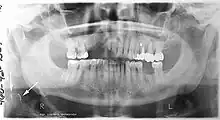

Panoramic radiographs have the capability to demonstrate a portion of the neck and display atheromas (calcifications in the carotid artery) which are an indication of both local and generalized (systemic) atherosclerosis. Atherosclerosis of the coronary arteries leading to myocardial infarction (heart attack), and atherosclerosis of the carotid artery leading to stroke are the number one and number three most common causes of death in the United States.[6]

There is interest to look at panoramic radiographs as a screening tool, however further data is needed with regards if it is able to make a meaningful difference in outcomes.[7]

Epidemiology: general public and high risk groups

Additional research projects have further determined the prevalence rate of these atheromas in the general population (3–5%)[8][9] and among high-risk groups (over 25% in: recent stroke victims,[10] individuals with obstructive sleep apnea syndrome,[11][12][13] postmenopausal women,[14] type 2 diabetics,[15][13][16] individuals with dilated cardiomyopathy,[17][13] and among individuals who have received radiotherapy directed at the neck,[18][19]). These findings have been corroborated by other several other researchers.[20][21][22][23][13]